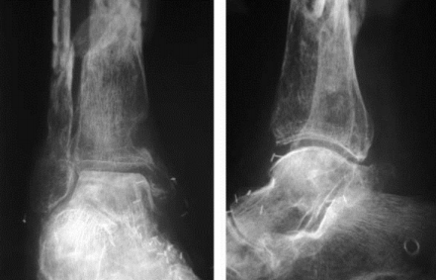

| What disease is this? What signs indicate this? | Osteomyelitis. Osteolysis (fragmentation), sequestra (dead/necrotic bone fragments floating in pus), rarefacation (loss of bone density). |